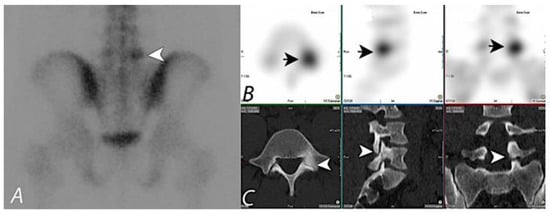

2. Oncologic Applications of Bone SPECT/CT